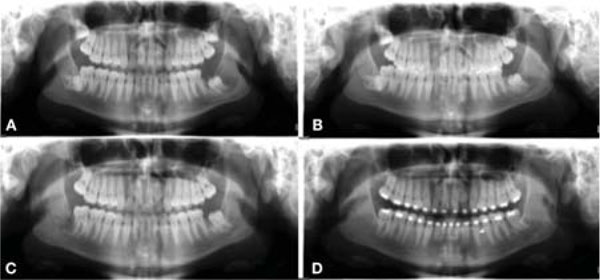

Significant regression of lesion size was observed on panoramic radiographs obtained during the decompression period. It was possible to diagnose that important anatomical structures, such as the inferior alveolar nerve, which were previously involved by the cystic lesions, were no longer involved, and adjacent new bone formation was observed between the anatomical structure and the cyst. An example of evidence of lesion size regression after decompression on panoramic radiographs is shown in Fig. (3).

Postoperative complications observed during treatment are shown in Table 3. Two patients who had paresthesia of the inferior alveolar nerve reported a return of nerve function within 6 months of the surgical procedure. There were no cases of pathological mandibular fracture or major complication. Mean follow-up was 59.57 months [range, 18-96 months]. No recurrence was observed during follow-up.